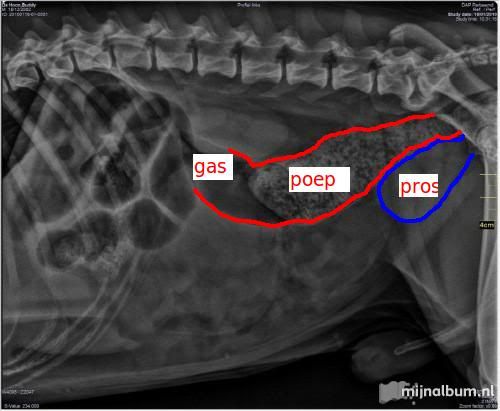

Dan de tweede foto. Zelfde kleuren. De prostaat líjkt iets kleiner te zijn, maar volgens mij is dat gezichtsbedrog. De blaas is namelijk veel voller, daardoor lijkt de prostaat kleiner maar volgens mij is die dat niet. Hoe dan ook, als je naar de dikke darm kijkt zie je dat de doorsnede daarvan naar achteren (rechts) toe steeds smaller wordt. Op de plaats waar de prostaat tegen de dikke darm aandrukt, is de diameter nog maar de helft van wat die zou horen te zijn. Naar voren toe zie je dat de dikke darm uitgezet (breder) is, waarschijnlijk omdat de poep er niet makkelijk uitkomt. Voor de poep zie je donkere vlakken in de dikke darm: dat is gas. Op basis van deze foto zou ik op zijn minst verwachten dat hij last heeft met poepen.